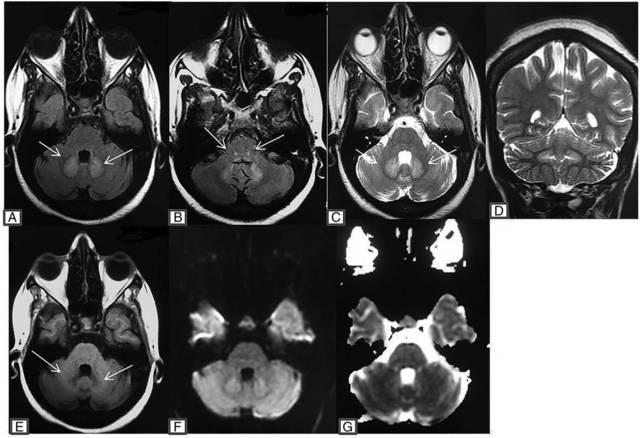

MRI 显示 T2 加权和 FLAIR 对称高信号,累及双侧齿状核和小脑深部白质(如图 1 A、C、D 白色箭头所示)和双侧脑桥背部的上橄榄核(如图 1b 白色箭头所示)。相应的区域在 T1 加权成像低信号(如图 1E 白色箭头所示)。在 DWI 未发现限制扩散,表观扩散系数图未见异常(如图 1F、G)。

图 1. MRI 显示 T2 加权和 FLAIR 对称高信号,累及双侧齿状核和小脑深部白质(如图 A、C、D 白色箭头所示)和背侧脑桥双侧橄榄核(如图 B 白色箭头所示)。相应的区域在 T1 加权成像低信号(如图 1E 白色箭头所示)。在 DWI 未发现限制扩散和表观扩散系数图未见异常(如图 F、G)